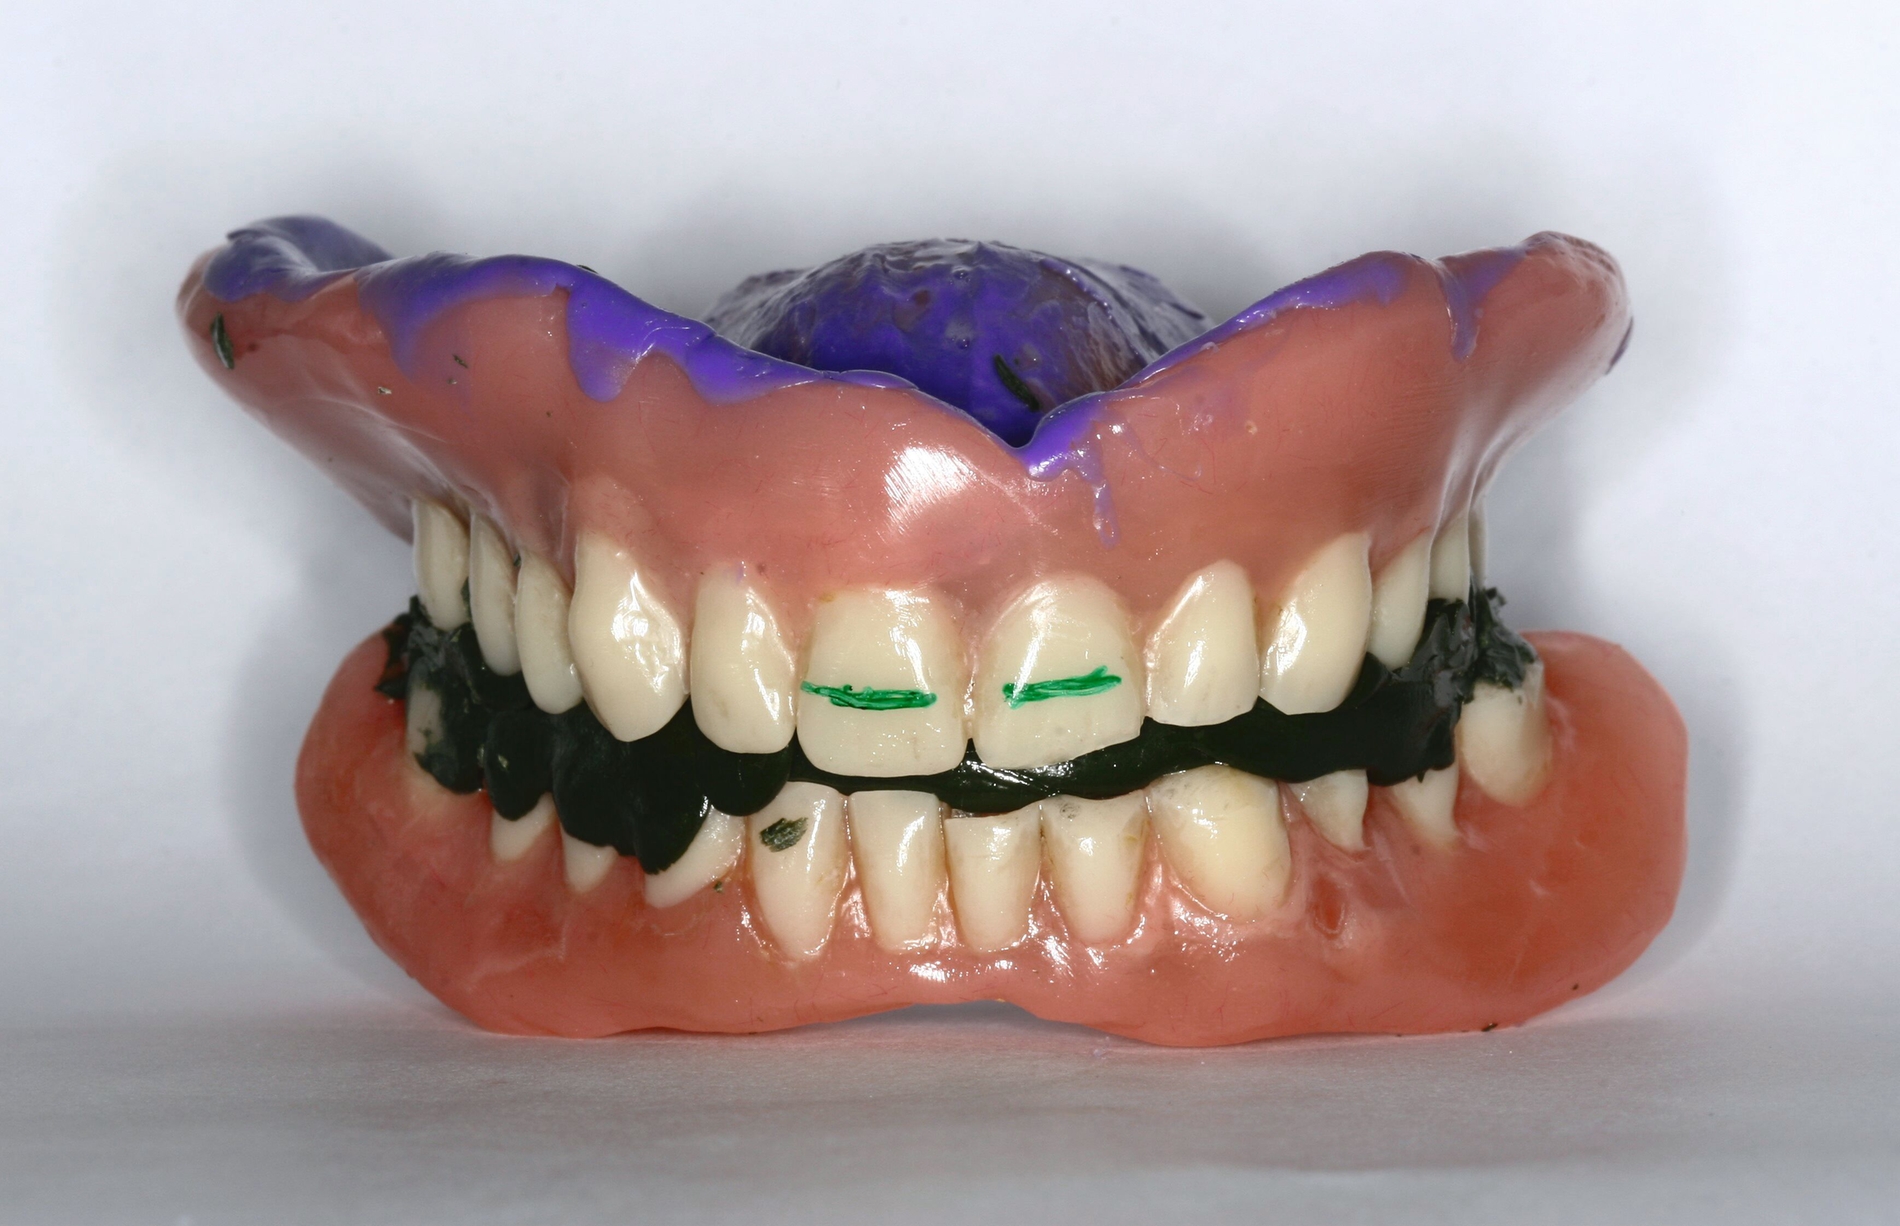

Bei Totalprothesen lässt sich dies beispielsweise durch die Replicadenture-Technik umsetzen. Die digitale Technologie hat dieses Verfahren nochmals vereinfacht. In der ersten Behandlungssitzung wird der bestehende Zahnersatz auf seine Mängel geprüft. Diese werden soweit möglich provisorisch am Zahnersatz korrigiert beziehungsweise an diesem markiert (Abbildung 9). Hierzu gehören der Aufbau der Stützkontakte und/oder die Registrierung der Prothesen in regelrechter Kieferrelation, die Ausformung und Anpassung der Prothesenränder und -basis ans Tegument, die Kennzeichnung der Lage der mittleren oberen Schneidezähne, aber auch die Übertragung der regelrechten Ausrichtung der Kauebene. Der so umgestaltete Zahnersatz kann mittels Intraoralscanner digitalisiert oder ins Labor zum Scannen gegeben werden. Nach der Informationsaufnahme werden die provisorischen Veränderungen wieder entfernt und der Patient erhält seinen unversehrten Zahnersatz zurück. Im Labor kann anhand der Datensätze der optimierten Prothesen ein neuer Zahnersatz konstruiert werden. Dieser sollte gegenüber dem alten Zahnersatz nur so viel Veränderung wie nötig aufweisen, damit eine einfache und schnelle Adaptation gelingt. In der zweiten Behandlungssitzung können die neuen Prothesen im Idealfall bereits eingesetzt werden.